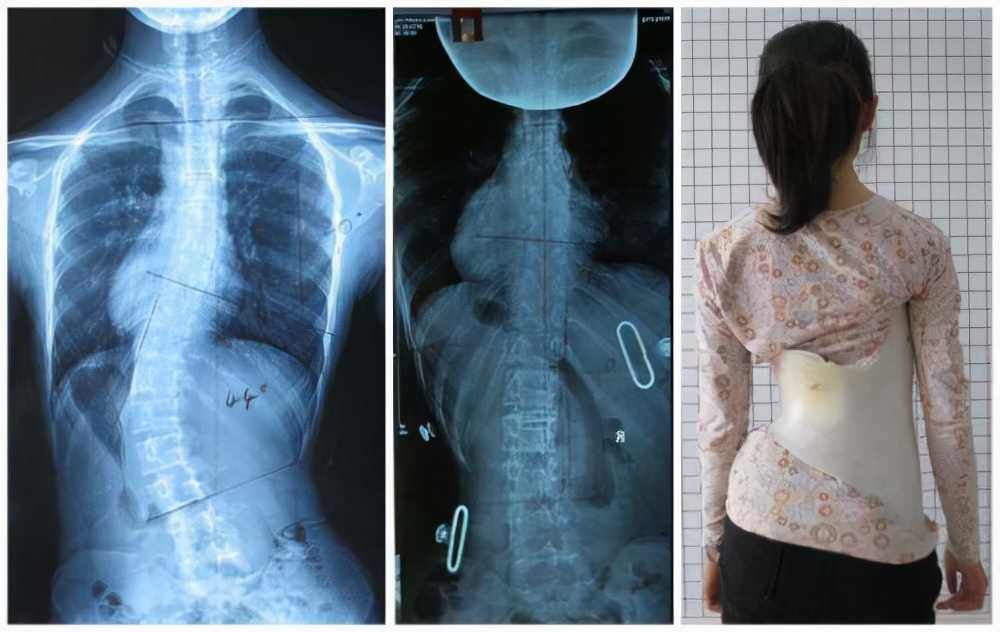

在我国脊柱侧弯的患者很多,据中华预防医学研究会统计,截止到2022年之前,约有500万不同程度的脊柱侧弯患者,这些患者中,大部分是中小学生、青少年。脊柱侧弯的程度有轻有重,有些患者在外观上和常人无异,但有些患者尤其是没有及时纠正的患者,情况十分严重,最后只能通过手术来治疗。

每个省、市的治疗花费不同,且病情严重程度不同,手术的费用也不相同。这是去年十月的一场手术,总花费12.8万报销7.5万左右,报销比例58%左右。从这则手术来看,脊柱侧弯手术费用并不是很高,且还能享受高额的报销,并不是很多患者说的治疗一次就会倾家荡产。

脊柱侧弯在青少年之间十分常见,尤其是特发性脊柱侧弯。脊柱侧弯前期外观表现不明显,但因青少年发育过快,经常有一年侧弯增加5-10度的例子。不仅会引起患者的体态变化,还会对其正常学习和生活造成非常大的影响,所以这种疾病要及早发现,尽早治疗。